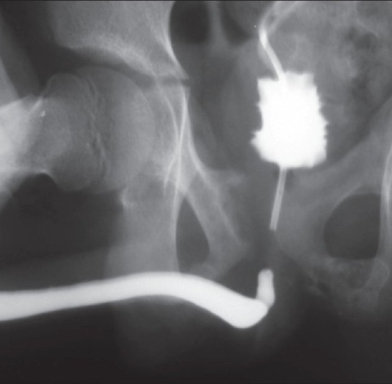

Contributors: Travis Barlock MD, Jeffrey Olson MS4 Feel free to use the cases below for your own practice. All of the scenarios are completely made up and designed to hit several teaching points. Case 1 25 M, presents to the ED with chest pain. Stabbing, started a few hours ago, substernal. Thinks it is GERD. After 2-3 minutes, pain worsens and radiates to the back. VS: BP 125/50 (Right arm 190/110). HR 120. RR of 18. Sat 98% on RA. Additional VS: Temp of 37.2, height of 6'5", BMI of 18. PMH: None, doesn't see a doctor. Meds: None FH: Weird heart thing (Mitral Valve Prolapse), weird lung thing (spontaneous pneumothorax), tall family members with long fingers and toes Physical Exam: Cards: Diastolic decrescendo at the RUSB, diminished S2. UE pulses are asymmetric, LE pulses are asymmetric, carotid pulses are asymmetric, BP is asymmetric MSK: Knees, elbows, and wrists are hypermobile. Imaging: CXR #1 normal, #2 widened mediastinum (no read yet but shows widened mediastinum), POCUS shows small effusion CTA/MRA doesn't come back until after the case. ECG: Sinus Tach Labs: NT-proBNP 500 pg/mL D-Dimer: 7000 ng/L CBC: Hemoglobin: 13.5 g/dL, WBC: 20,000/µL, Platelets: 250,000/µL Chem 7: Na 138, K, 5.7, Cl 102, Bicarb 17, BUN 45, Creatinine: 3.5 mg/dL, Glucose: 180 LFTs: Albumin 2.4, Total protein 5.5, ALP: 140, AST: 3500, ALT: 2800, TBili: 3.2, DirectBili: 2.4, Ca: 7.8 LDH: 2200 PT: 20.5, INR: 2.2, Fibrinogen: 170 5th gen High-Sensitivity Troponin: <3 Lactate: 7 mmol/L VBG: pH 7.22, paCO2 28, bicarb 15 Notes: Can have patient crash somewhere in middle and show 2nd xray Case 2: A 67-year-old female is brought to the ED by her daughter due to progressive weakness, confusion, and fatigue that have worsened over the past week. Unable to get out of bed and has become increasingly lethargic. Also having some nausea, constipation. The daughter denies any preceding illness, recent trauma, or travel. Does not know her meds but will head home to get them after talking with you. VS: BP 88/55 mmHg, HR 110, RR 20, O2 Sat 98% on room air. Additional VS: Temp 36.8°C. PMH: Hypertension, osteoarthritis, and depression. Physical exam: General: Thin, somnolent but arousable. HENT: Dry mucous membranes Neuro: Confused, A&Ox1 (self), hyporeflexia Labs (Includes many that would not return in the ED in case you want to take this case forward to the floor) CBC: WBC 9,500, Hb 16.5, Hct: 50%, Platelets 220,000 Chem7: Na 129, K 2.1, Cl 95, HCO3 34, Creatinine 1.6, BUN 40, Glucose 115 LFTs: normal Magnesium: 1.1 Calcium: 10.8 mg/dL (corrects to 12.8) iCal: 3.2 Phosphate: 2.3 mg/dL Albumin: 2 BUN:Cr ratio: 25 VBG: pH: 7.49, PaCO2 45, HCO3: 34 Lactate: 2.8 Serum Osmolality: 276 mOsm/kg (Osmolal gap of 2) Urine Osmolality: 550 mOsm/kg Urine Sodium (UNa): 10 mEq/L (low). Urine Potassium (UK): 25 mEq/L (elevated). Urine Chloride (UCl): 12 mEq/L (low). Urine Magnesium (UMg): 20 (Elevated). Urine Calcium (UCa): 50 in 24 hrs (Low) 100 cc of urine with foley FeNa Plasma renin activity: 15 mg/mL/hr (elevated), Aldosterone: 25 ng/dL (Elevated), ADH: Elevated, Diuretic screen: Positive for thiazides PTH: 8 (low), HsTrop: 32, Cortisol and ACTH: Normal. EKG: Hypokalemia features CXR: Normal Renal US: shows stones Improves with fluids Note: Can have daughter return with med list at some point including HCTZ, ibuprofen, and sertraline Case 3: Patient Presentation EMS Report: A 27-year-old male involved in a high-speed motorcycle collision is brought to the emergency department by EMS. The patient was found unconscious at the scene with evidence of severe thoracic and extremity trauma. He was intubated en route for airway protection due to altered mental status (GCS 7). VS: HR 130, BP 90/60, RR: bagging at 12 bpm, satting 88% on 100% FiO2 Primary Survey Airway: Endotracheal tube in place. Breathing: Decreased breath sounds on the left side with visible chest asymmetry and paradoxical chest wall movement. Circulation: Mottled extremities noted, with significant deformity of the right thigh. Pulses are diminished in the right leg Disability: GCS remains 7 (E1 V2 M4). Pupils equal and reactive. Exposure: Full-body examination reveals an open fracture of the right femur, multiple abrasions, and bruising over the chest wall. Vent alarms Peak Inspiratory Pressure (PIP) 40 cm H₂O (elevated) Plateau Pressure (Pplat) 35 cm H₂O (elevated) EtCO₂ (End-Tidal CO₂) 55 mmHg High-Pressure Alarm Triggering frequently Glucose 120 CBC: Hgb 8.9, Hct 27, WBC 14.2, platelets 220,000 VBG: pH 7.28, pCO2 33, bicarb 18, lactate 4.5 CXR with tension pneumothorax Patient improves after chest tube, pigtail catheter, or needle decompression. Ready to be transferred upstairs and O2 starts tanking again Vent alarms- second episode Peak Inspiratory Pressure (PIP) 35 cm H₂O (elevated) Plateau Pressure (Pplat) 30 cm H₂O (elevated) EtCO₂ (End-Tidal CO₂) 20 mmHg HR: 140, satting 84%, temp 38.5, ABG: pH 7.32, pCO₂ 30 mmHg, pO₂ 60 mmHg on 100% FiO₂, HCO₃⁻ 18 mmol/L (hypoxemia and metabolic acidosis). D-dimer: Elevated Thrombocytopenia: Platelets 90,000/µL. US shows blown right ventricle ECG shows new RBBB CT PE: Ground glass opacities, consolidation, centrilobular nodules, septal thickening, and fat-attenuating lesions. Note: Management is largely supportive care so once the diagnosis is made, end the case. References Carroll MF, Schade DS. A practical approach to hypercalcemia. Am Fam Physician. 2003 May 1;67(9):1959-66. PMID: 12751658. Coelho SG, Almeida AG. Marfan syndrome revisited: From genetics to the clinic. Rev Port Cardiol (Engl Ed). 2020 Apr;39(4):215-226. English, Portuguese. doi: 10.1016/j.repc.2019.09.008. Epub 2020 May 18. PMID: 32439107. Palmer BF. Metabolic complications associated with use of diuretics. Semin Nephrol. 2011 Nov;31(6):542-52. doi: 10.1016/j.semnephrol.2011.09.009. PMID: 22099511. Reed MJ. Diagnosis and management of acute aortic dissection in the emergency department. Br J Hosp Med (Lond). 2024 Apr 30;85(4):1-9. doi: 10.12968/hmed.2023.0366. PMID: 38708978. Roberts DJ, Leigh-Smith S, Faris PD, Blackmore C, Ball CG, Robertson HL, Dixon E, James MT, Kirkpatrick AW, Kortbeek JB, Stelfox HT. Clinical Presentation of Patients With Tension Pneumothorax: A Systematic Review. Ann Surg. 2015 Jun;261(6):1068-78. doi: 10.1097/SLA.0000000000001073. PMID: 25563887. Rothberg DL, Makarewich CA. Fat Embolism and Fat Embolism Syndrome. J Am Acad Orthop Surg. 2019 Apr 15;27(8):e346-e355. doi: 10.5435/JAAOS-D-17-00571. PMID: 30958807. Produced by Jeffrey Olson, MS4 Special thanks to Evan Fisch MD Get your tickets to Tox Talks Event, Sept 11, 2025: https://emergencymedicalminute.org/events-2/ Donate: https://emergencymedicalminute.org/donate/